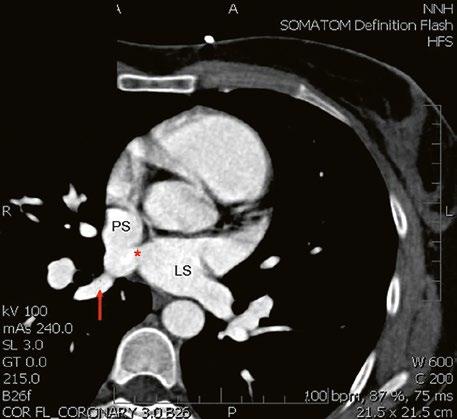

Obr. 45.11 CT angiografie, defekt typu sinus venosus superior je označen hvězdičkou, anomální pravá horní plicní žíla ústící do horní duté žíly je označena šipkou

PS – pravá síň, LS – levá síň